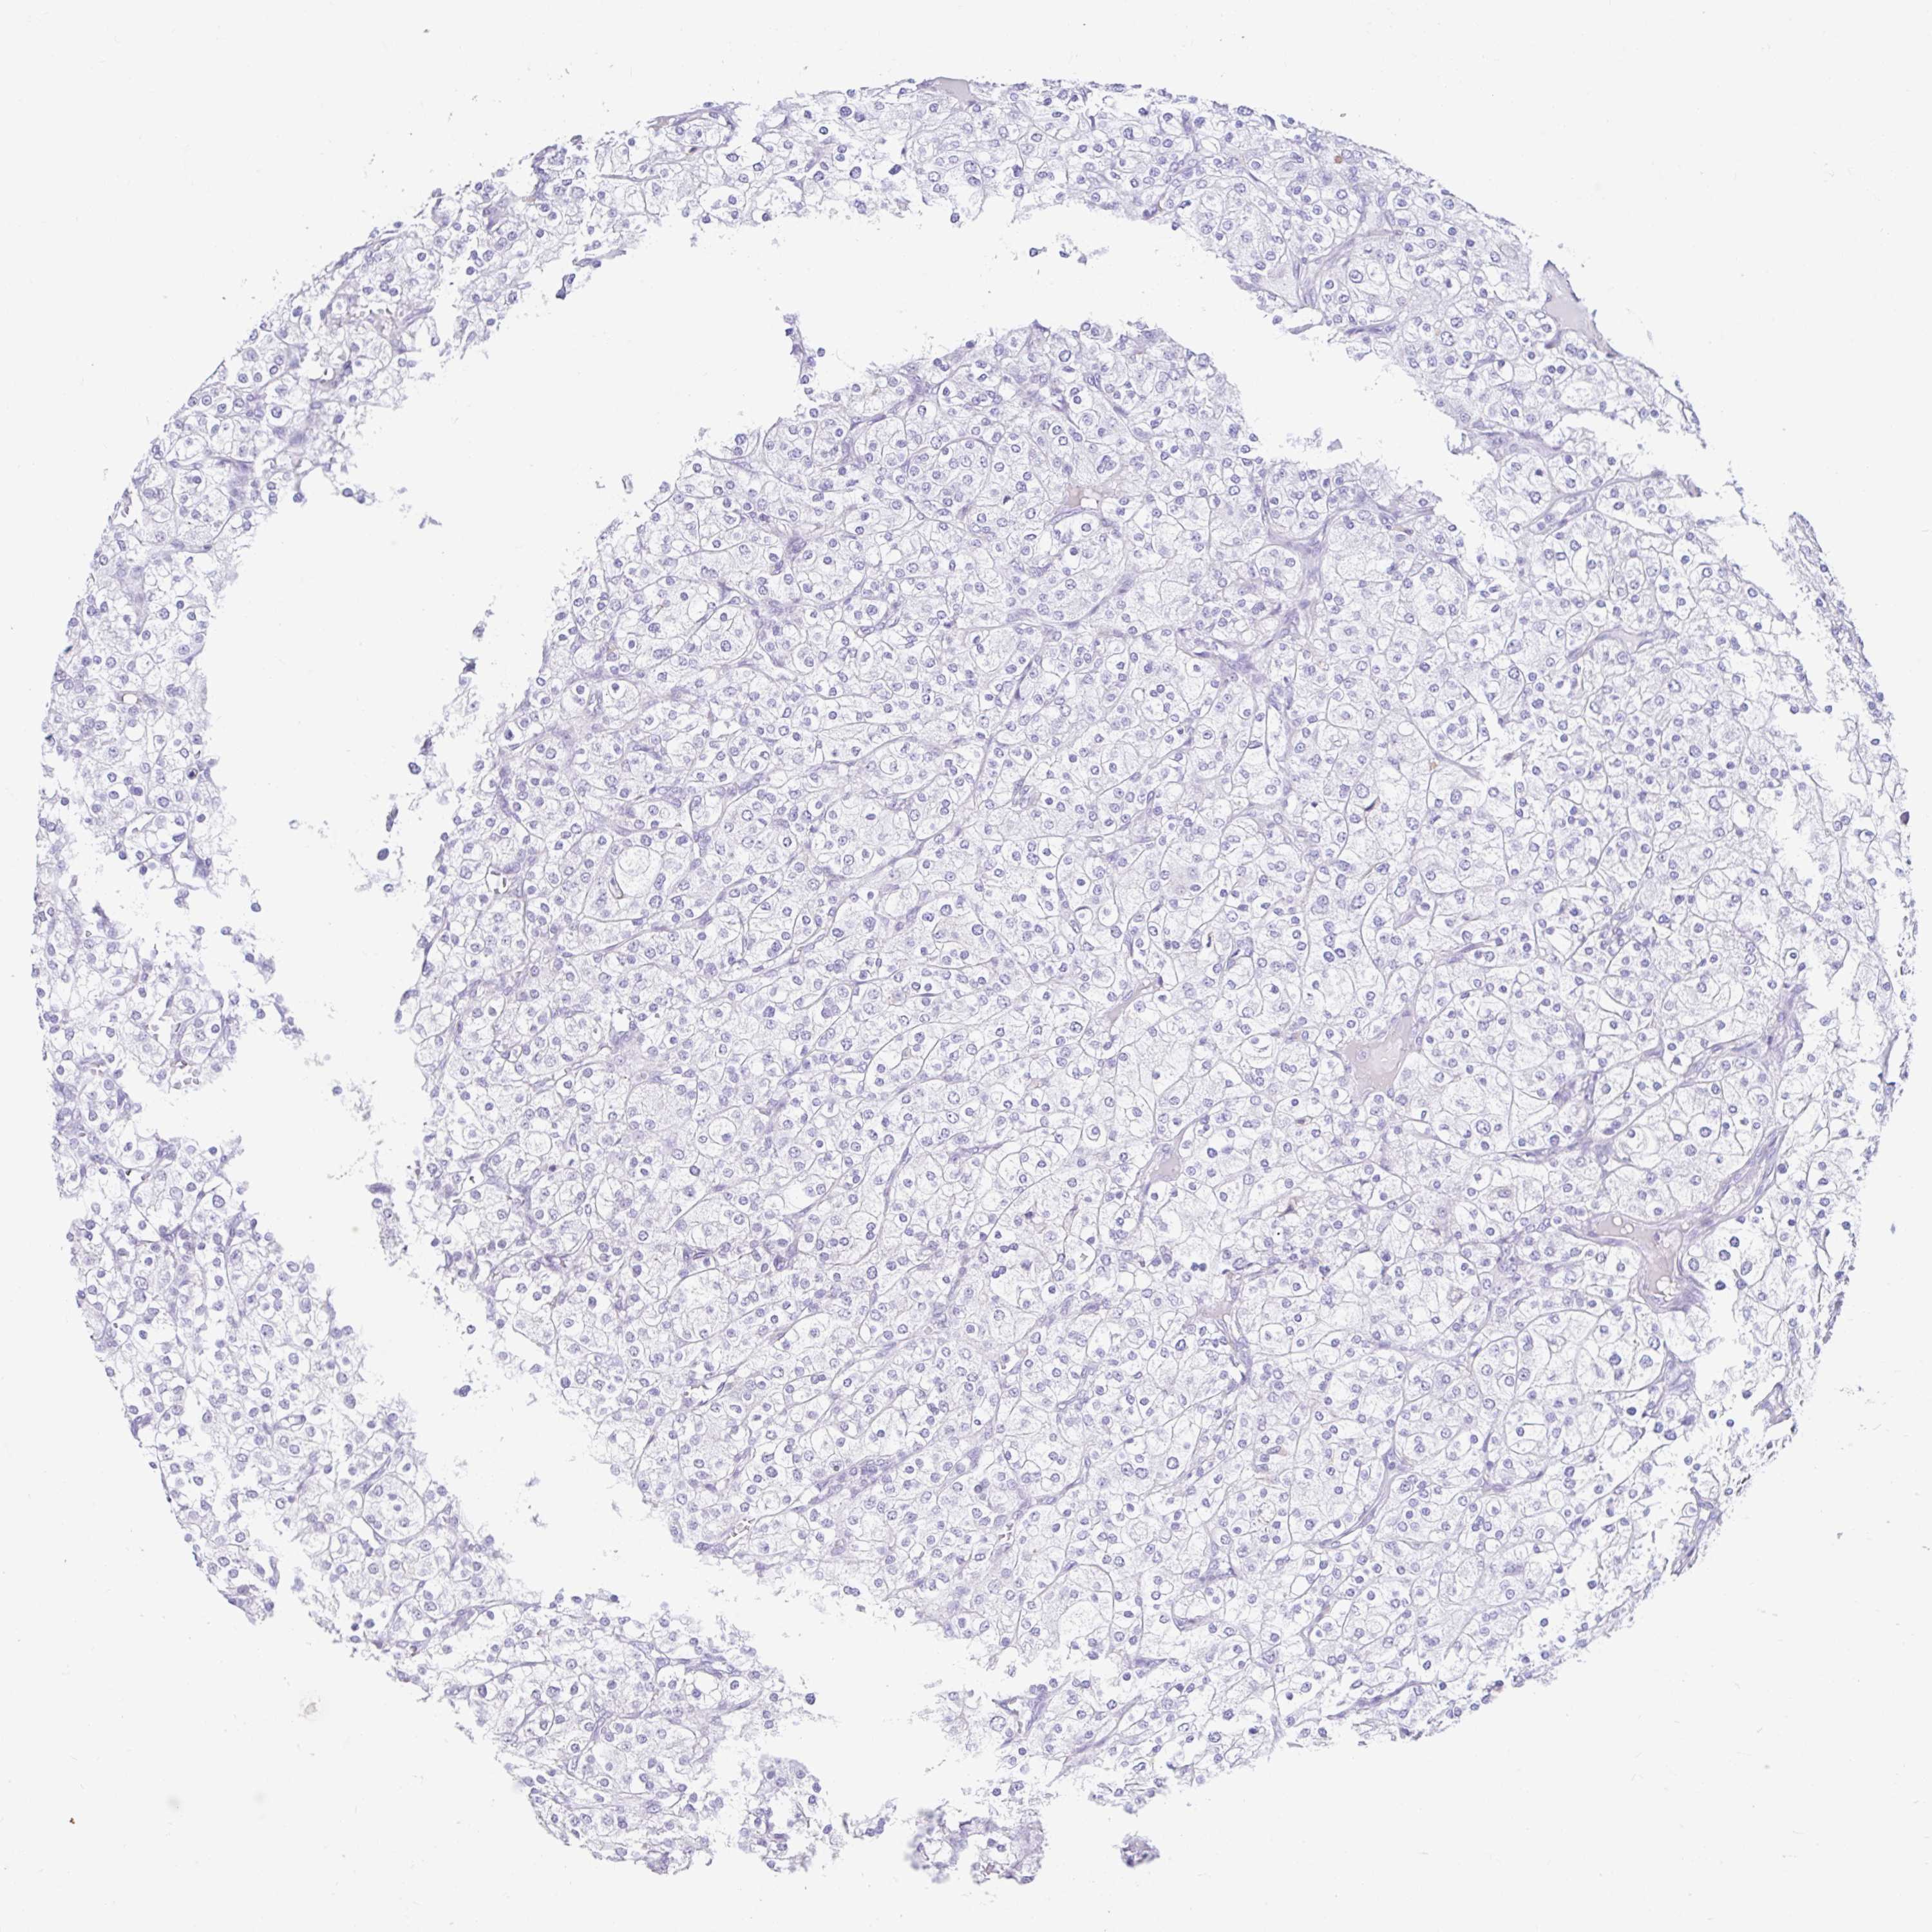

KIDNEY RENAL CLEAR CELL CARCINOMA (TCGA) - Interactive survival scatter ploti

The Survival Scatter plot shows the clinical status (i.e. dead or alive) for all individuals in the patient cohort, based on the same data that underlies the corresponding Kaplan-Meier plots. Patients that are alive at last time for follow-up are shown in blue and patients who have died during the study are shown in red.

The x-axis shows the expression levels (FPKM) of the investigated gene in the tumor tissue at the time of diagnosis. The y-axis shows the follow-up time after diagnosis (years). Both axes are complimented with kernel density curves demonstrating the data density over the axes. The top density plot shows the expression levels (FPKM) distribution among dead (red) and alive patients (blue). The right density plot shows the data density of the survived years of dead patients with high and low expression levels respectively, stratified using the cutoff indicated by the vertical dashed line through the Survival Scatter plot. This cutoff is automatically defined based on the FPKM cutoff that minimizes the p-score. The cutoff can be changed by dragging the vertical line or by entering a cutoff value in the square labeled "Current cut-off".

Under the Survival Scatter plot the p-score landscape (black curve; left axis) is shown together with dead median separation (red curve; right axis). Dead median separation is the difference in median mRNA expression between patients who have died with high and low expression, respectively. It is calculated as follows: median FPKM expression of dead patients with high expression - median FPKM expression of dead patients with low expression. This is intended to aid the user in visually exploring custom cutoffs and the associated p-scores and dead median separation.

Individual patient data is displayed and can be filtered by clicking on one or more of the category buttons on the top of the page. Categories describing expression level and patient information include: high, low, alive, dead, female, male and tumor stages. The scale of the x-axis can be toggled between linear and log-scale by clicking on the "x log" button. Mouse-over function shows TCGA ID, patient information and mRNA expression (FPKM) for each patient.

& Survival analysisi

Kaplan-Meier plots summarize results from analysis of correlation between mRNA expression level and patient survival. Patients were divided based on level of expression into one of the two groups "low" (under cut off) or "high" (over cut off). X-axis shows time for survival (years) and y-axis shows the probability of survival, where 1.0 corresponds to 100 percent.

DCAF17 is not prognostic in Kidney Renal Clear Cell Carcinoma (TCGA)

Best expression cut offi

Based on the FPKM value of each gene, patients were classified into two groups and association between prognosis (survival) and gene expression (FPKM) was examined. The best expression cut-off refers the FPKM value that yields maximal difference with regard to survival between the two groups at the lowest log-rank P-value. Best expression cut-off was selected based on survival analysis .

When clicking on this number, the vertical dashed line indicating cut-off, the interactive survival plot, and the Kaplan-Meier curve will be adjusted to show results based on the best expression cut-off.

: 2.63

P scorei

Log-rank P value for Kaplan-Meier plot showing results from analysis of correlation between mRNA expression level and patient survival.

N/A

TCGA RNA samplesi

RNA-seq data is reported as average FPKM (number Fragments Per Kilobase of exon per Million reads), generated by the The Cancer Genome Atlas (TCGA) .

Normal distribution across the dataset is visualized with box plots, shown as median and 25th and 75th percentiles. Points are displayed as outliers if they are above or below 1.5 times the interquartile range. FPKM values of the individual samples are presented next to the box plot.

Average pTPM 4.0

Number of samples 521